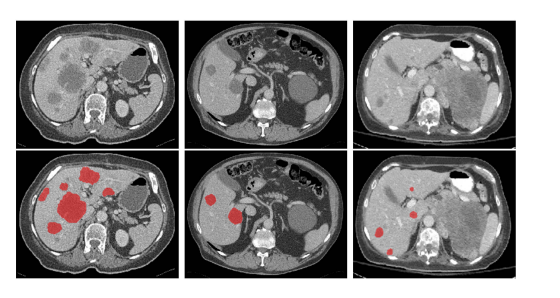

Fig. 11. Examples of tumor segmentation results by models trained with Couinaud segment annotations using our proposed method on the MSD08 test dataset. The green ones denote the ground truths, while the red ones denote the segmentation results using our method.

图11。使用我们提出的方法,通过Couinaud区段注释训练的模型在MSD08测试数据集上的肿瘤分割结果示例。绿色部分表示真实标签,红色部分表示使用我们方法的分割结果。

Fig. 12. Examples of tumor segmentation results by models trained with Couinaud segment annotations on the LiTS test dataset.

图12。使用Couinaud区段注释训练的模型在LiTS测试数据集上的肿瘤分割结果示例。